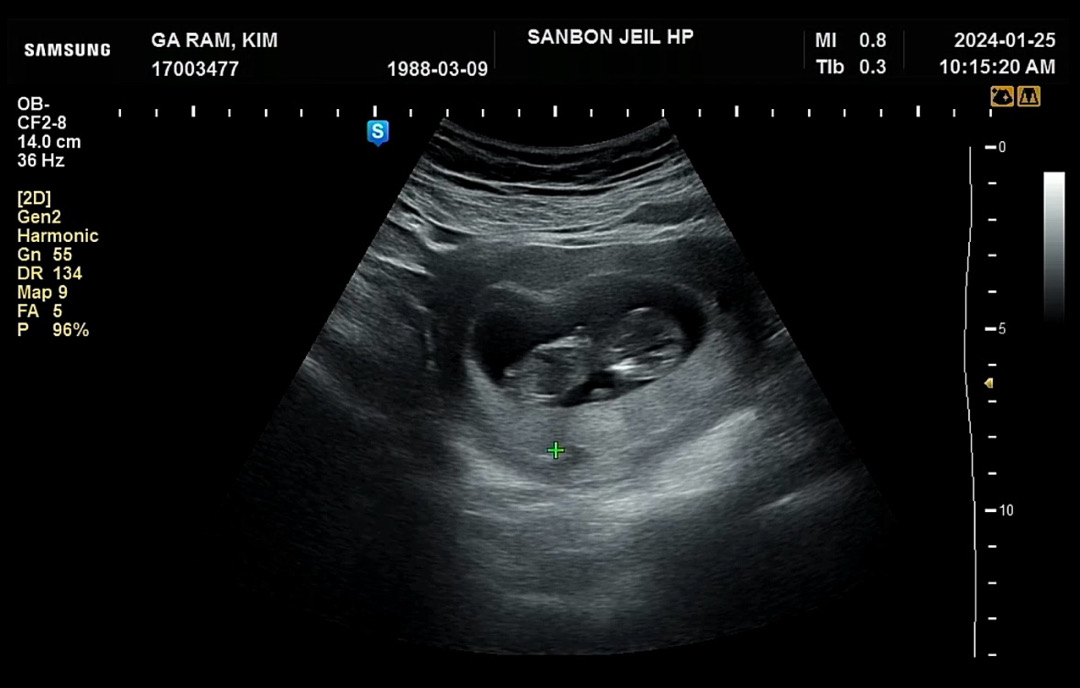

11주4일 피비침

저번주부터 갑자기 피고임 생기더니 피가 비쳐서 좀 불안했었어요(입원을 권유받았는데 집에서 휴식했어요) 10주4일에 크기는 3.53센치 였고 심박수두 다행히 좋았어요 오늘 11주4일 일주일후 피고임이 어떤지 확인하러 병원진료 받고 왔는데 크기는 5.17센티로 2센치 가까이 자랐더라고요☺️ 내심 좀 불안했는데 자궁경부에 아주 조그만한 용종이 있어서 그것때문에 출혈원인일수도 있으니 여전히 눕눕을 많이 하라네요 😭 누워있기 너무 힘듭니다 허리도 너무 아프구 그래도 딱콩이 건강한거 보고 와서 한숨 놓이네요 다음주에 1차 기형아검사도 잘 나왔으면 좋겠습니다!